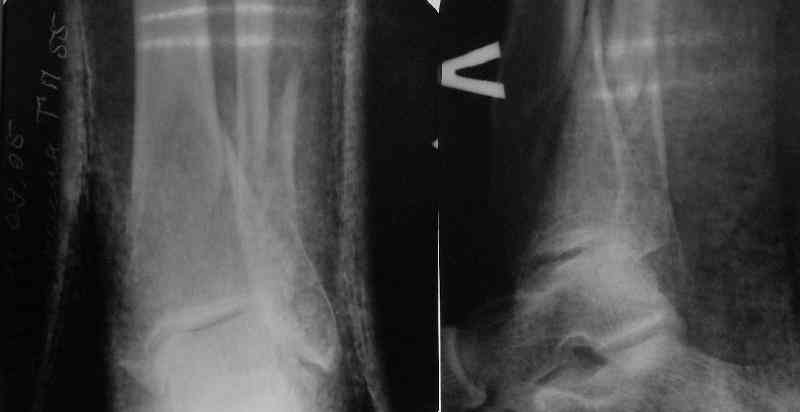

Направили к нам пациентку 35 лет с переломом дистального отдела костей голени.

У нас сделали снимок сзахватом обоих суставов - еще и проксимальный метафиз сломан. Чем бы у вас фиксировали такой перелом? Как его правильно закодировать по классификации АО?

From the Xrays it seems as though the proximal fracture is relatively undisplaced. I thought that Poller screws were mostly used to prevent displacement of the fracture while the nail was being inserted. In this case I would think that you could hold the reduction temporarily either with a clamp, crossed K wires or a lag screw. Then insert the nail and place a proximal blocking screw only if you need to. Will the proximal locking screws fix the proximal fragment? Are you going to fix the fibula?

It is often a problem nailing upper tibial fractures. There is a tendency to apex anterior angulation as well as valgus alignment. Your entry point on the AP view seems to have been kept the same. How did you manage to maintain alignment? Any intra-operative pictures of your technique?

The lateral view shows your entry point to be quite posterior and I think this is recommended to avoid anterior angulation. Were you concerned about intra-articular penetration?

Overall an excellent post-op x-ray. Well done.